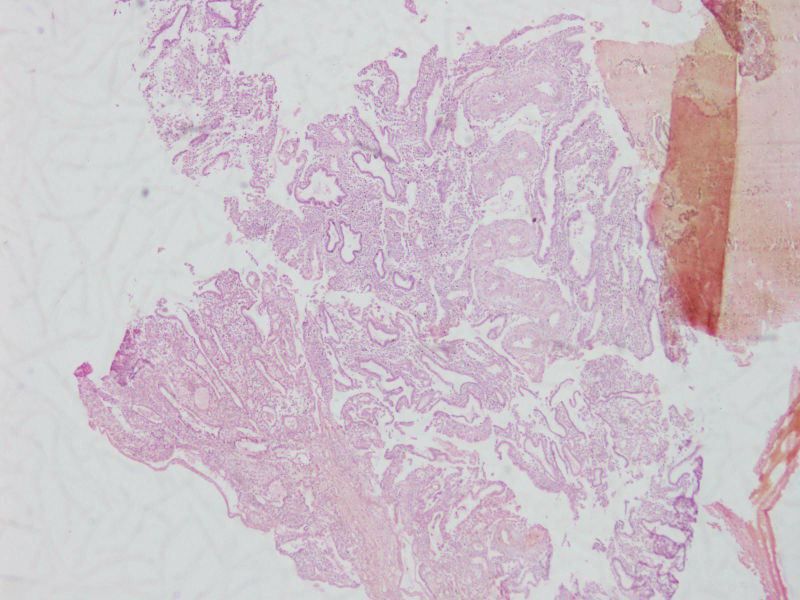

图1

女44,阴道不规则流血一月

流血期宫内膜